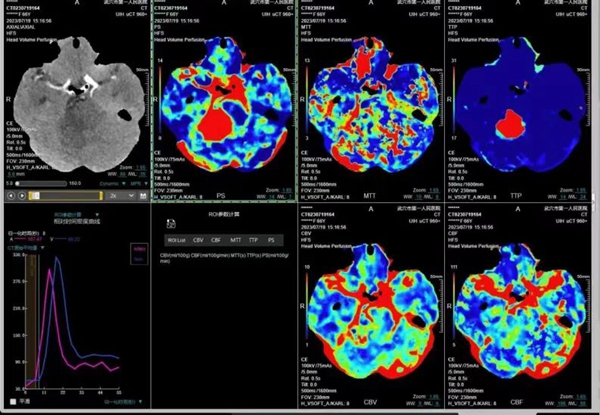

“60秒”4D一站式检查脑卒中 脑血管疾病筛查更精准

该设备还可实现单圈扫描的全脑覆盖成像,60秒即可完成头颅灌注检查,采用宽体采集进行头部平扫、动态CTA及CTP成像,一次检查即可获得全脑平扫图像、动静脉造影图像和灌注图像。

结合集成脑灌注分析、4D动静脉动态评估等高级后处理手段,不仅可应用于急诊缺血性脑卒中的影像评估,还可助力脑血管畸形、脑动脉瘤等其他脑血管病的结构和功能评估。